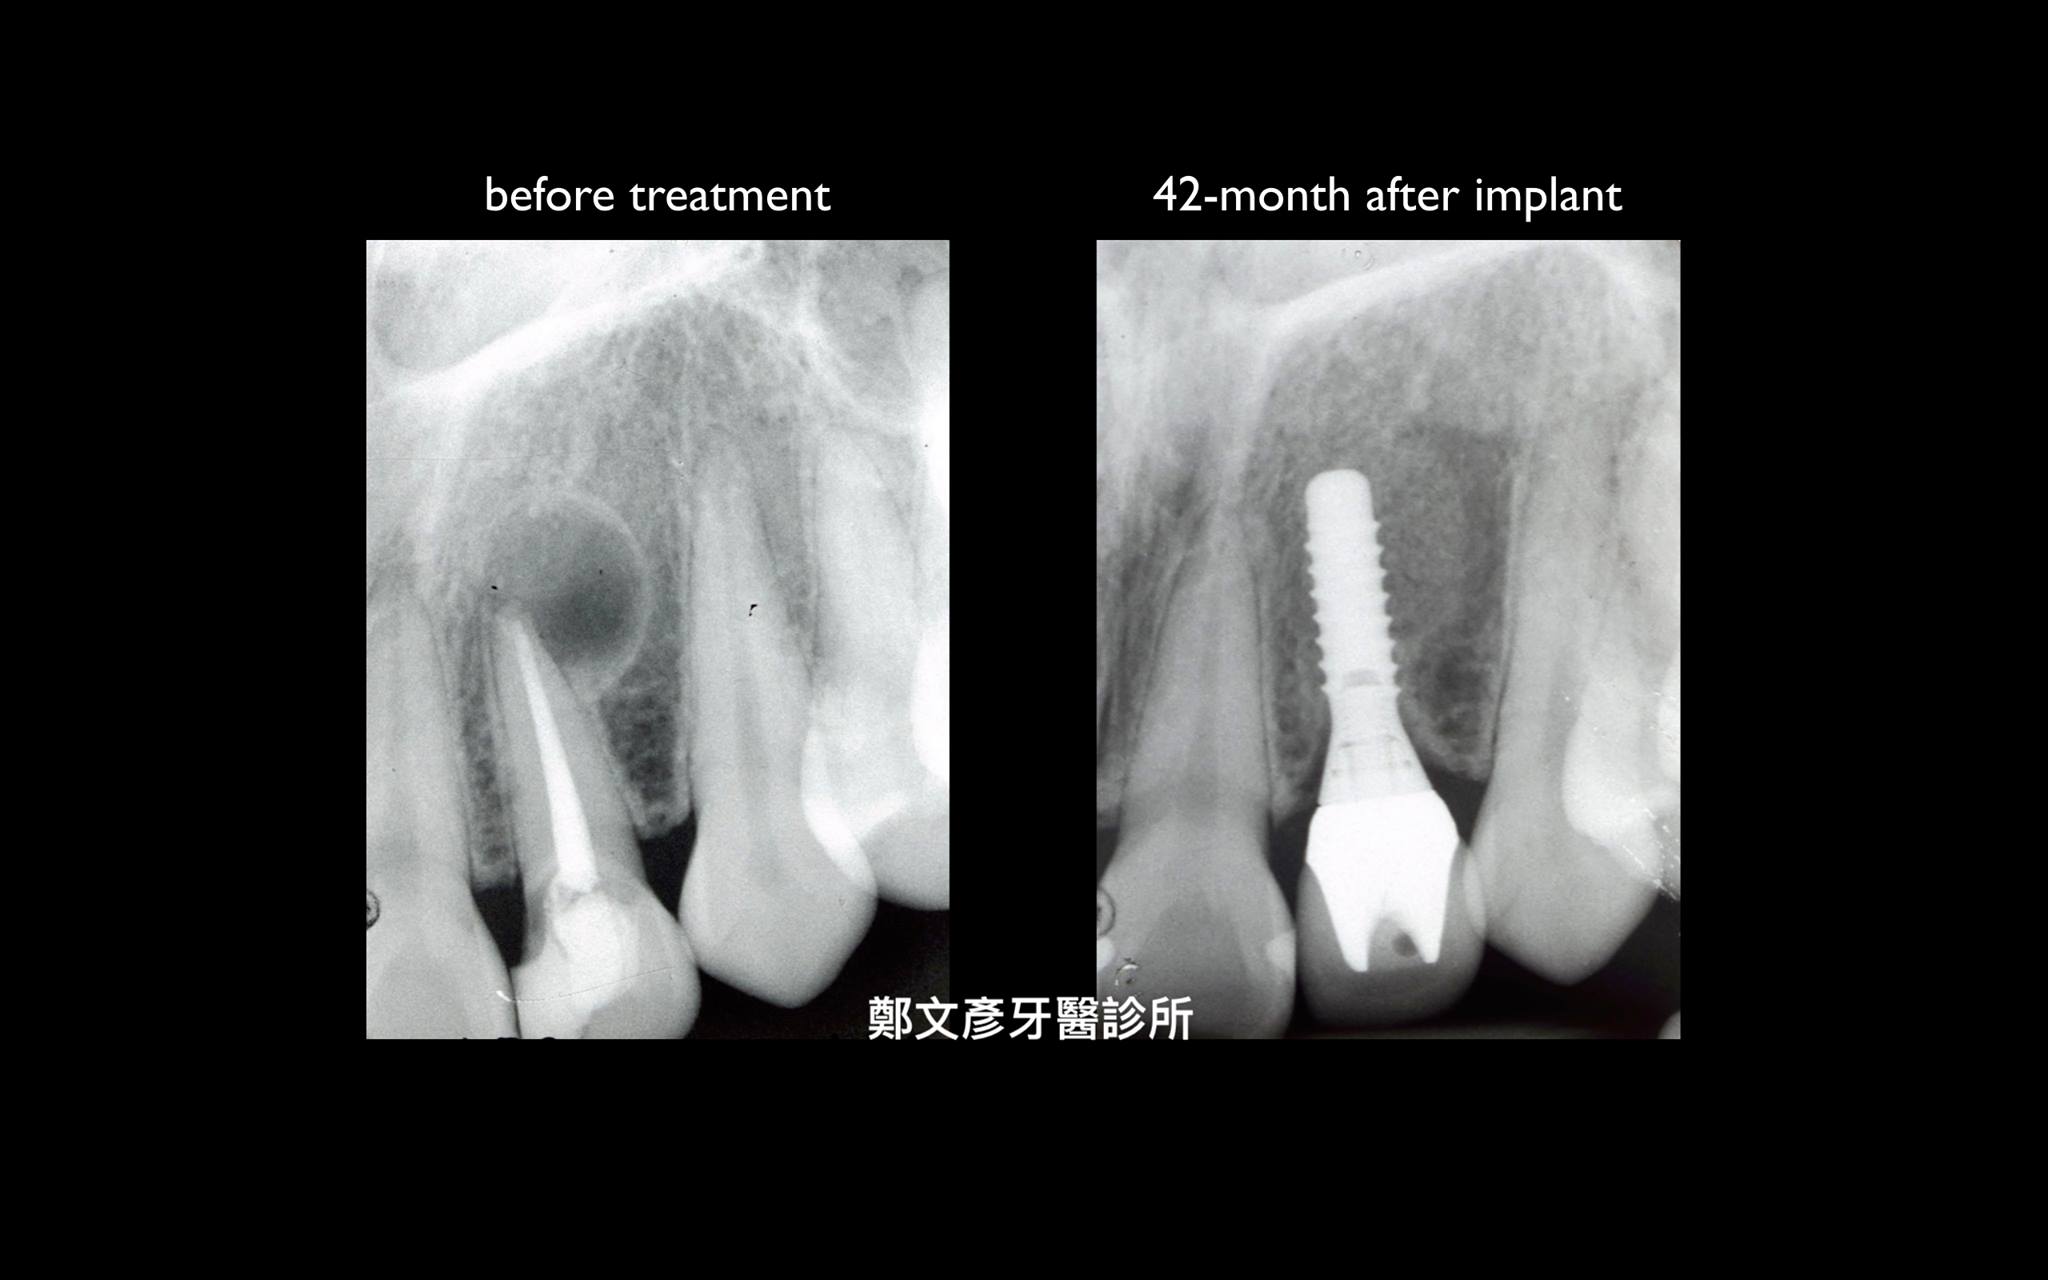

前牙植牙美學及軟組織轉移

Role of granulation tissue in socket preservation